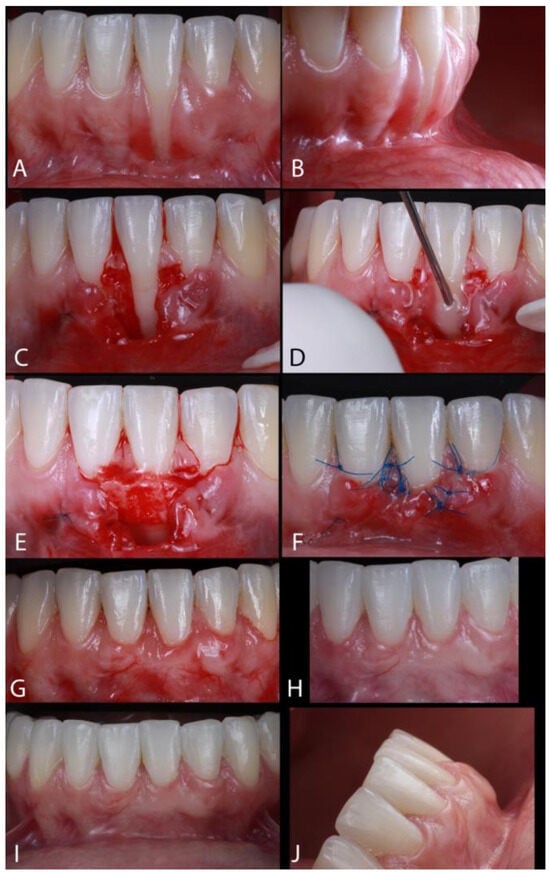

The Treatment of Gingival Recessions in the Lower Anterior Region Associated with the Use/Absence of Lingual-Fixed Orthodontics Retainers: Three Case Reports Using the Laterally Closed Tunnel Technique and Parallel Incision Methods

- Sculean, A.; Allen, E.P. The Laterally Closed Tunnel for the Treatment of Deep Isolated Mandibular Recessions: Surgical Technique and a Report of 24 Cases. Int. J. Periodontics Restor. Dent. 2018, 38, 479–487. [Google Scholar] [CrossRef] [PubMed]

- Kahn, S.; Araujo, I.T.E.; Dias, A.T.; Souza, A.B.; Chambrone, L.; Fernandes, G.V.O. Histologic and histomorphometric analysis of connective tissue grafts harvested by the parallel incision method: A pilot randomized controlled trial comparing macro- and microsurgical approaches. Quint. Int. 2021, 52, 2021. [Google Scholar]

- Vrushali, A.; David, W.; Jules, M. Treatment of a mandibular anterior lingual recession defect with minimally invasive laterally closed tunneling technique and sub-epithelial connective tissue graft. Int. Arch. Oral Maxillofac. Surg. 2018, 2, 17. [Google Scholar] [CrossRef]